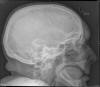

Higroma frontal bilateral